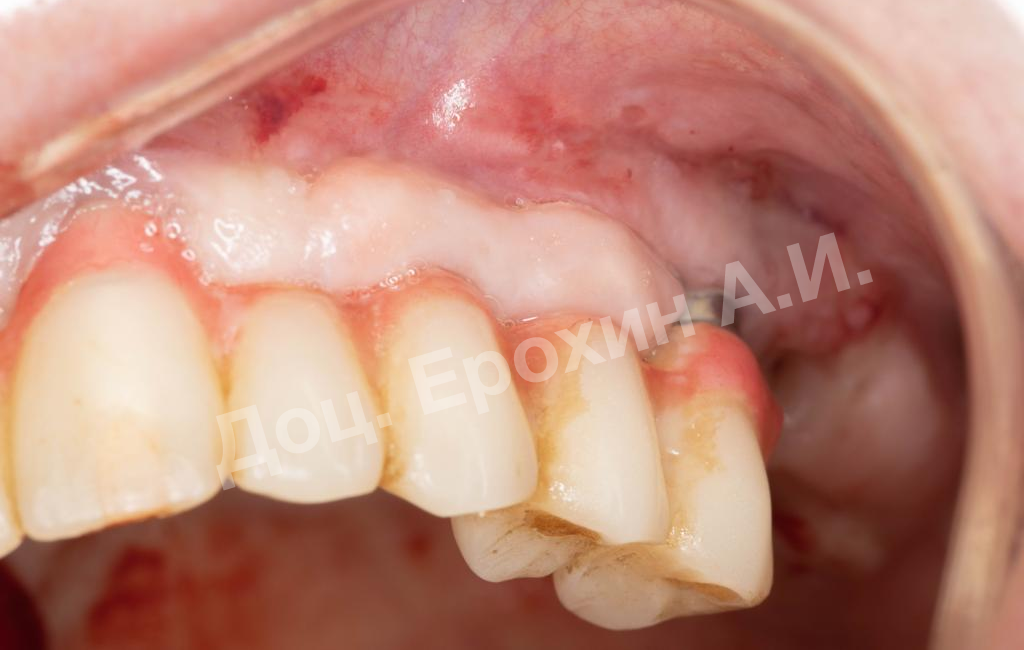

В данном клиническом случае мы можем наблюдать эффект так называемого наползающего прикрепления (creeping attachment), когда десна после удаления момента натяжения начинает сама наплывать на ранее оголенные корни зубов и имплантаты.

На фото видно, что в первом сегменте с 2.5-3 мм оголение корня осталось меньше 1 мм, в области имплантата 21 рецессия самоустранилась, а в области имплантата 26 рецессия до операции была 4.5 мм, а после сократилась до 2 мм.